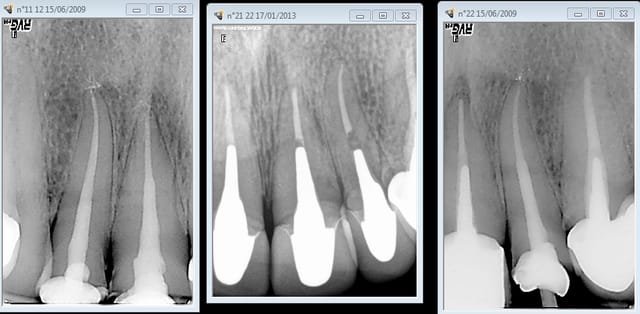

Une effraction pulpaire ça s'anticipe, ou alors tu n'as pas de radio rétro-alvéolaire dans ton cabinet ?